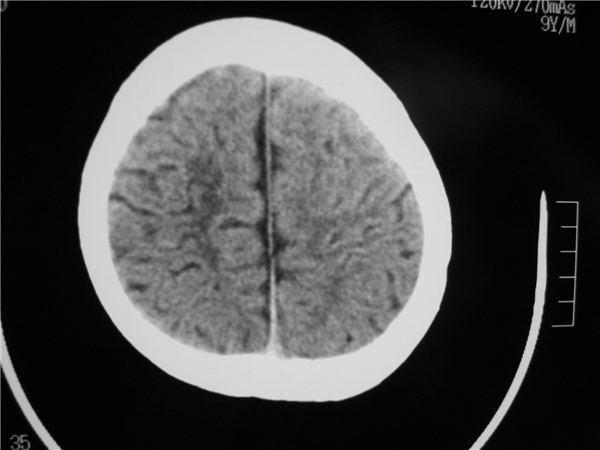

以下是引用余辉在2009-9-2 8:06:00的发言:[br]右侧侧脑室扩大,脑髓质量明显减少,胼胝体区结构不良,脑沟增深。考虑右侧大脑萎缩伴胼胝体发育不良(可能后遗改变(hie史?)),请查病史。第三脑室四脑室扩张,应该有脑积水存在

以下是引用dyqct在2009-9-1 21:57:00的发言:[br]右侧侧脑室扩大,脑髓质量明显减少,脑沟增深。考虑右侧大脑萎缩(可能后遗改变),请查病史。

以下是引用hguox在2009-9-1 21:52:00的发言:[br]胼胝体发育不全

以下是引用拾荒者在2009-9-2 20:53:00的发言:[br]右侧侧脑室扩大,脑髓质量明显减少,胼胝体区结构不良,脑沟增深。考虑右侧大脑萎缩伴胼胝体发育不良。至于是否合并脑炎,可结合实验室检查或脑脊液检查。